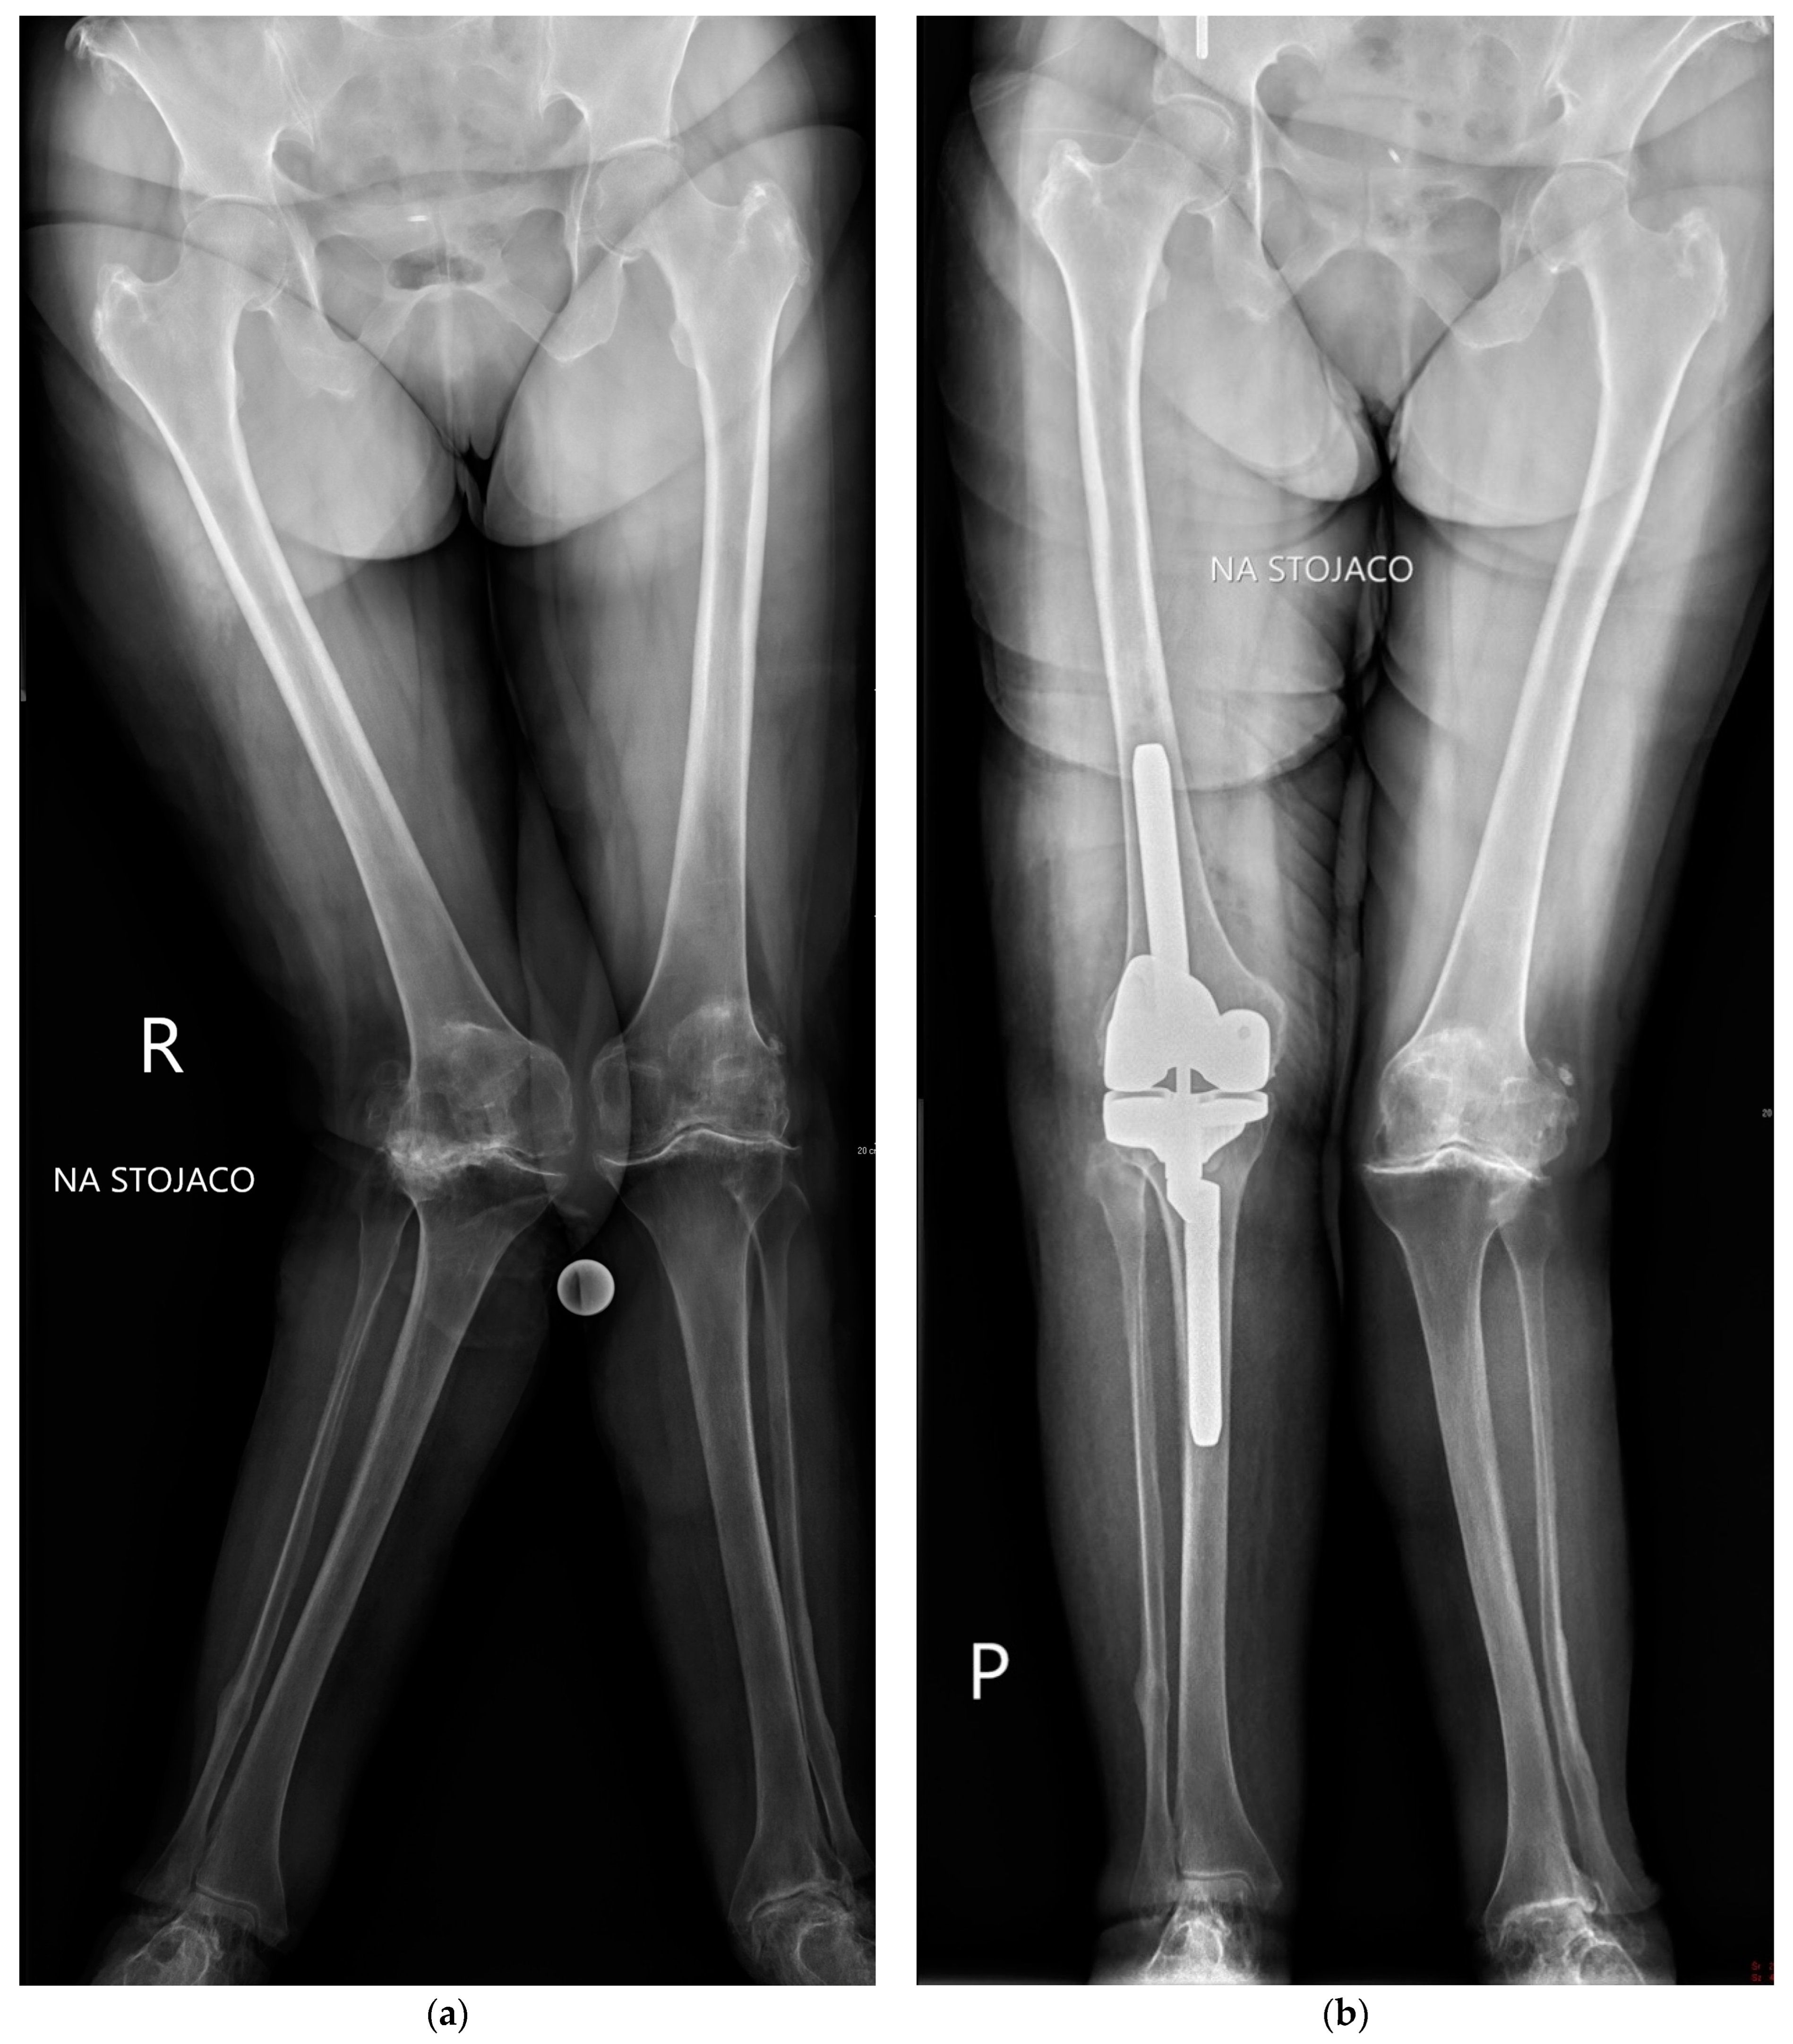

2.2. Surgical Approach

| Pre-op valgus (°) | 21.6 | 7.2 | 16.6 | 6.3 | 4.31 | <0.001 | 2.69 | 7.24 | 0.71 |

| Post-op valgus (°) | 6.0 | 2.9 | 5.2 | 2.3 | 1.71 | 0.089 | −0.12 | 1.68 | 0.28 |

| Angle of correction (°) | 15.6 | 7.5 | 11.4 | 6.8 | 3.52 | 0.001 | 1.87 | 6.63 | 0.58 |